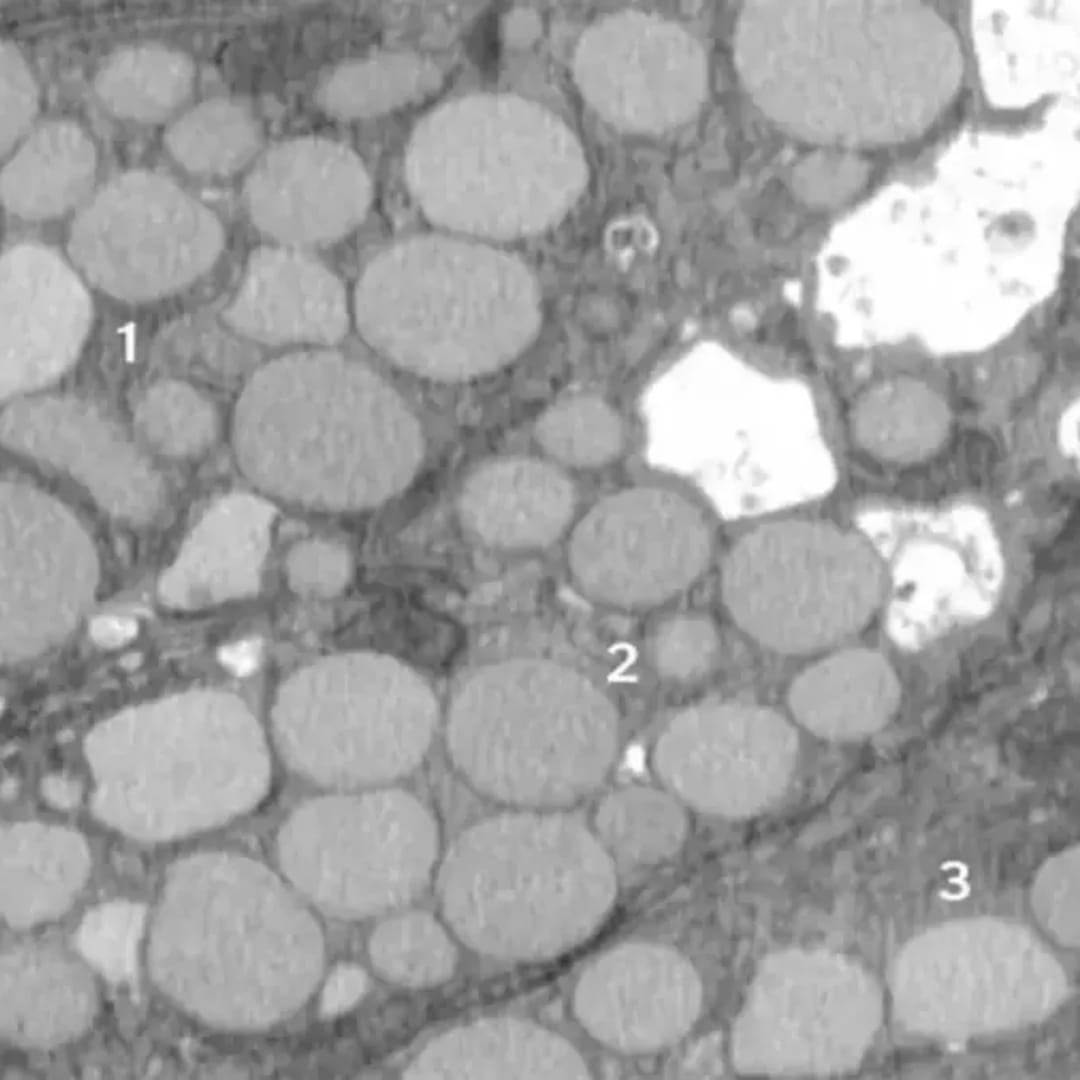

St. Louis, Amerika Serikat - Para peneliti dari Washington University dan Baylor College menemukan sebuah proses baru dalam sel yang membantu penyembuhan luka dengan cara berubah menjadi seperti sel induk. Proses ini dinamakan cathartocytosis, yang berarti sel mengeluarkan komponen lama dengan cara seperti 'muntah' agar bisa mulai memperbaiki diri dengan cepat.

Studi yang dilakukan pada tikus dengan luka di lambung tersebut menunjukkan bahwa ketika sel mengalami cedera, mereka akan melakukan pembersihan cepat terhadap bagian-bagian sel yang sudah tua dan rusak. Ini membuat sel bisa memperbarui diri dan memperbaiki jaringan lambung yang terluka secara lebih efisien.

Mekanisme cathartocytosis merupakan bagian dari proses yang lebih besar bernama paligenosis, di mana sel dewasa menjadi lebih ‘muda’ dan bersifat seperti sel stem yang mampu memperbanyak diri untuk mengganti sel yang rusak. Proses ini mirip dengan cara tubuh melakukan regenerasi jaringan, tetapi dengan cara yang lebih cepat.

Walaupun proses ini membantu penyembuhan, ada sisi negatif yang harus diwaspadai. Pengeluaran limbah sel yang cepat dan berlebihan ini bisa memperburuk peradangan dan bahkan memicu kanker jika terjadi secara kronis. Debu atau sisa limbah sel ini menumpuk di sekitar area luka dan bisa menghambat penyembuhan serta merusak jaringan lebih lanjut.